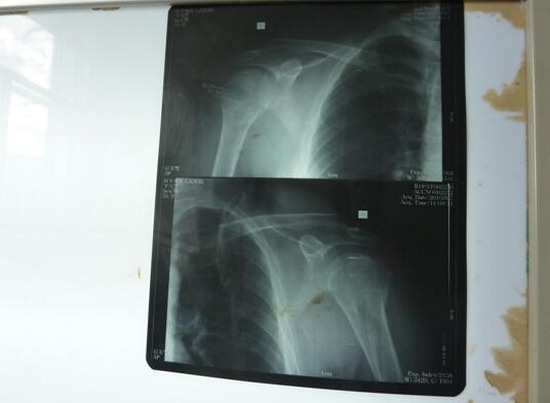

众所周知,骨科医生手术离不开器械和设备,在这里,每台骨科手术都需要他亲自找钢板、螺钉和克氏针等材料。材料不合适,他亲自修整;没有C臂,手术完全靠经验。有时实在想打退堂鼓,但是每每看到患者期盼的眼神和淳朴的话语,他是真心无法拒绝。两月来,他听到患者最多的一句话就是:胡主任,您就放心大胆去做,做好了,我们感谢您,做不好,这是神的旨意,我们不怪您。听到这样的话,谁会忍心拒绝,谁不尽心尽力。每次手术,他都尽量带着科室的医生去做,至今,已参加带教手术20余例,其中新技术新项目6例,分别是:三踝骨折并胫骨下端骨骺分离切开复位内固定术;胫骨开放性粉碎性骨折清创复位外固定架固定术;取骨术与植骨术;肱骨外科颈骨折切开复位内固定术;骨盆骨折切开复位内固定术;巴通骨折切开复位内固定术。股骨颈骨折人工股骨头置换术是阿里地区第二例手术,在当地也产生了很大的社会影响。他参加带教的常规手术有:锁骨骨折切开复位内固定术;肱骨髁上骨折切开复位内固定术;股骨干骨折切开复位内固定术;胫骨干骨折切开复位内固定术;内踝骨折切开复位内固定术;内、外踝骨折切开复位内固定术;多指畸形矫形术;清创缝合术;断指残端修整术;腱鞘囊肿切除术等。指导或参与手法复位石膏固定10余人次。通过带教,规范了骨科手术的操作技术,提高了手术操作水平和技巧。时至今日,没有一例因为技术原因而转走的骨科病人,基本做到中组部提出的中病不出地区的援藏目标。

肱骨外科颈及肱骨头骨折切复内固定